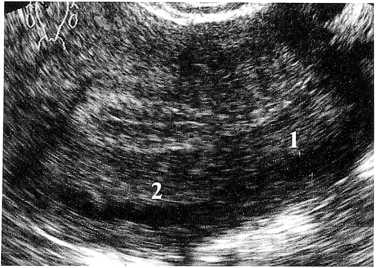

При исследовании в В—режиме миометрий у пациенток с ВРВМ представлялся неоднородным, в его структуре определяли множественные анэхогенные включения округлой, овальной или вытянутой форм, располагающиеся преимущественно на границе среднего и наружного отделов (рис. 3).

Рис. 3. Больная М., 34 года, 12 день менструального цикла. Расширение аркуатной вены при ВРВМ. Продольное ТВ—сканирование: 1 — аркуатная вена до 5 мм в диаметре; 2 — миометрий

При изменении плоскости сканирования округлые образования приобретали вытянутую форму, превращаясь в трубчатые структуры. При исследовании в ЦДК и ЭД они равномерно заполнялись цветом (рис. 4).